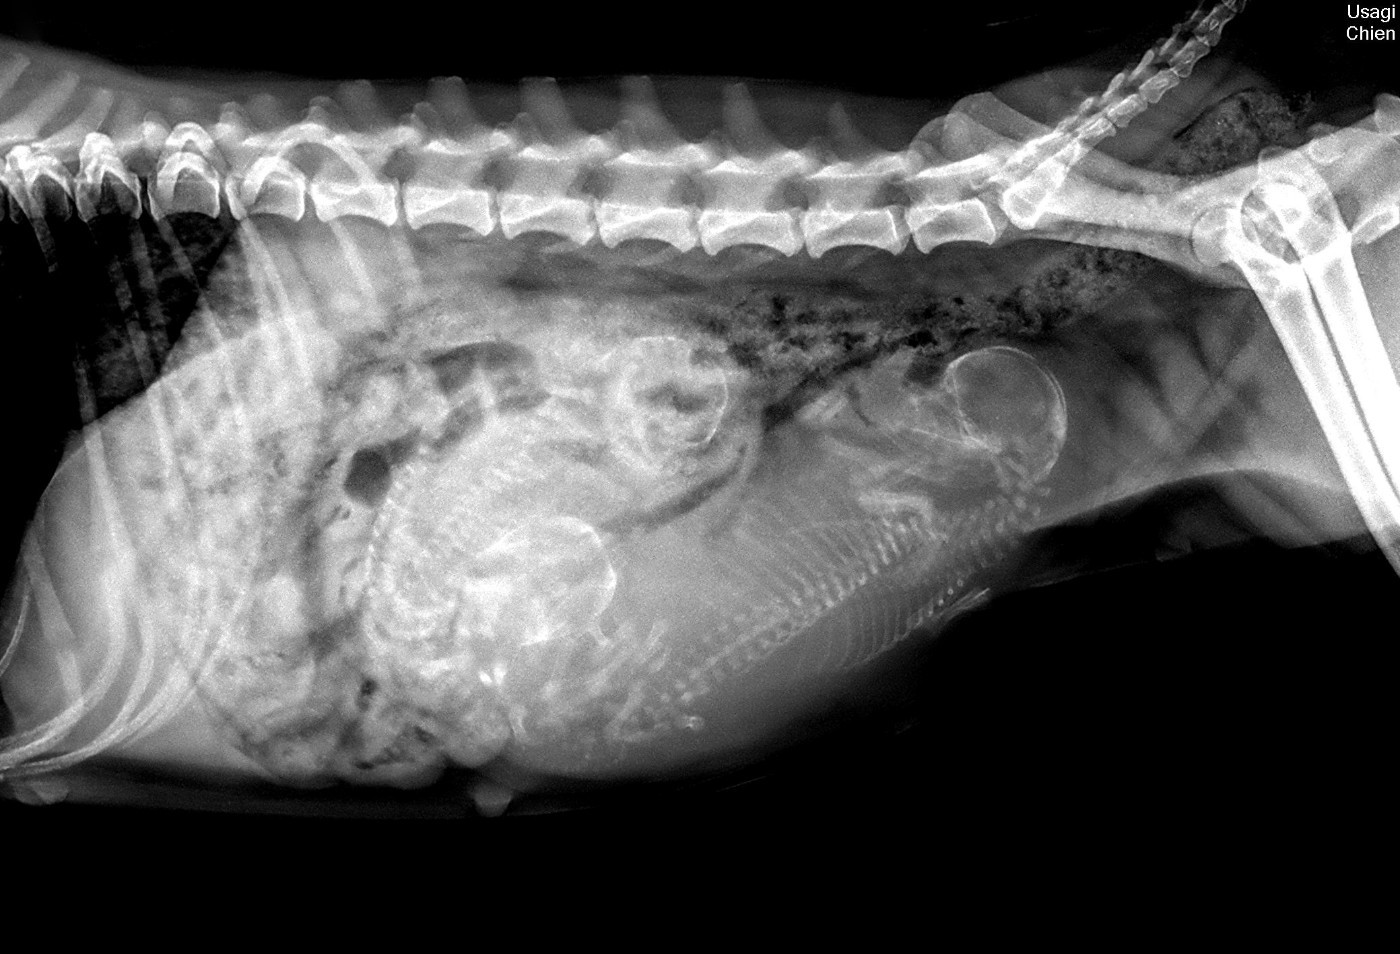

Litter "B" 02/02/2026 Présentation de la portée Radiographie de comptage Naissance de 4 filles le 02/02/26 Bao - 5 jours Boke - 5 jours Botan - 5 jours Bamboo - 5 jours Portée "B" - 18 jours, auprès de leur mère Portée "B" - 18 jours Bao - 24 jours Boke - 24 jours Botan - 24 jours Bamboo - 24 jours Les filles - 4,5 semaines Bao - 4,5 semaines Boke - 4,5 semaines Botan - 4,5 semaines Bamboo - 4,5 semaines Bao - 4,5 semaines Boke - 4,5 semaines Botan - 4,5 semaines Bamboo - 4,5 semaines Bao - 5,5 semaines Bao - 5,5 semaines Boke - 5,5 semaines Boke - 5,5 semaines Botan - 5,5 semaines Botan - 5,5 semaines Bamboo - 5,5 semaines Bamboo - 5,5 semaines Bao renommée Baya - 7 semaines Boke renommée B'Kanao - 7 semaines Botan renommée B'Nala - 7 semaines Bamboo renommée Bento - 7 semaines Baya - 7 semaines Kanao - 7 semaines Nala - 7 semaines Bento - 7 semaines Baya - 8 semaines Baya - 8 semaines Kanao - 8 semaines Nala - 9 semaines Bento - 9 semaines Baya - 9,5 semaines Kanao - 9,5 semaines Nala - 9,5 semaines Bento - 9,5 semaines Nala, Bento, Kanao & Baya - 9,5 semaines